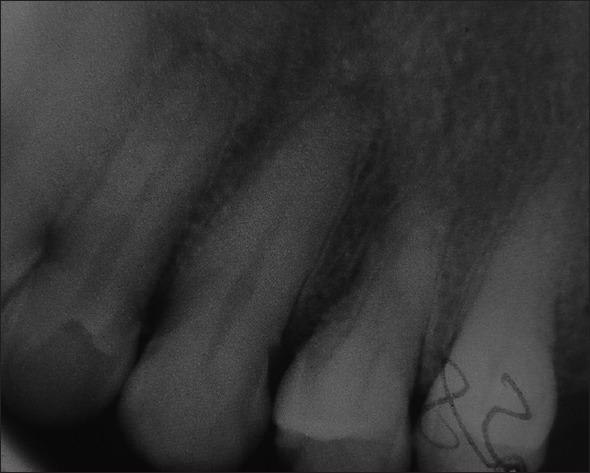

Odontogenic tumors (OTs) arising from the periodontium are quite rare. Squamous OT (SOT) is one such neoplasm which has an exceedingly rare occurrence. According to the literature, there have been very few reported cases of SOT with a very small percentage involving the gingiva. Most of the times, these tumors are located within the bone, only a very few peripheral cases been noted so far. Although predominantly benign, the possibility of a malignant transformation prevails. Our case describes a rare presentation of a peripheral SOT involving the upper anterior gingiva in a 59-year-old patient, which presented clinically as a firm and fibrotic swelling. An excisional biopsy was performed as a part of surgical management and for microscopic evaluation to confirm the clinical diagnosis. A soft tissue graft was harvested from an edentulous area to cover the deficit at the surgical site. The patient was evaluated at periodic intervals to assess the healing outcome and for any recurrence of the lesion.